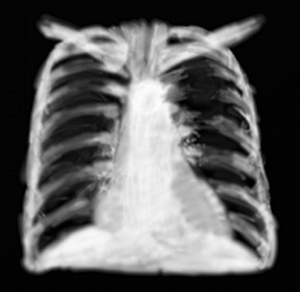

RP pneumomédiastin

3ème grand syndrome compressif du thorax, et le plus rare; la survenue brutale d’air dans le médiastin (appelé aussi emphysème médiastinal) entre les poumons et le coeur est une urgence dramatique car elle évolue souvent très vite, et on comprend le diagnostic souvent très (trop) tard. L’emphysème médiastinal risque de créer un choc obstructif par compression du coeur, et une détresse respiratoire haute quand l’air fuse vers les espaces celluleux du cou.

L’image radiographique est une hyperclarté linéaire bilatérale, mais souvent difficile à percevoir des 2 côté en même temps, en une ligne bordant le coeur. Elle forme une sorte de fausse enveloppe.

Le plus souvent c’est une perforation de l’oesophage thoracique (iatrogène post endoscopique, syndrome de Boerhaave) qui est la cause de la brèche aérique dans le médiastin, ou une rupture de la trachée ou des bronches. Elles peuvent survenir en contexte traumatique ou non. En fonction de la hauteur de la brèche, l’image peut être haute ou basse en faux pneumopéricarde (qui est encore plus rare).

Lésion rare donc, hormis en traumatologie où elle est associée à d’autres lésions gazeuses comme un pneumothorax et un emphysème sous-cutané.

Dans le doute le scanner thoracique répond aux questions.